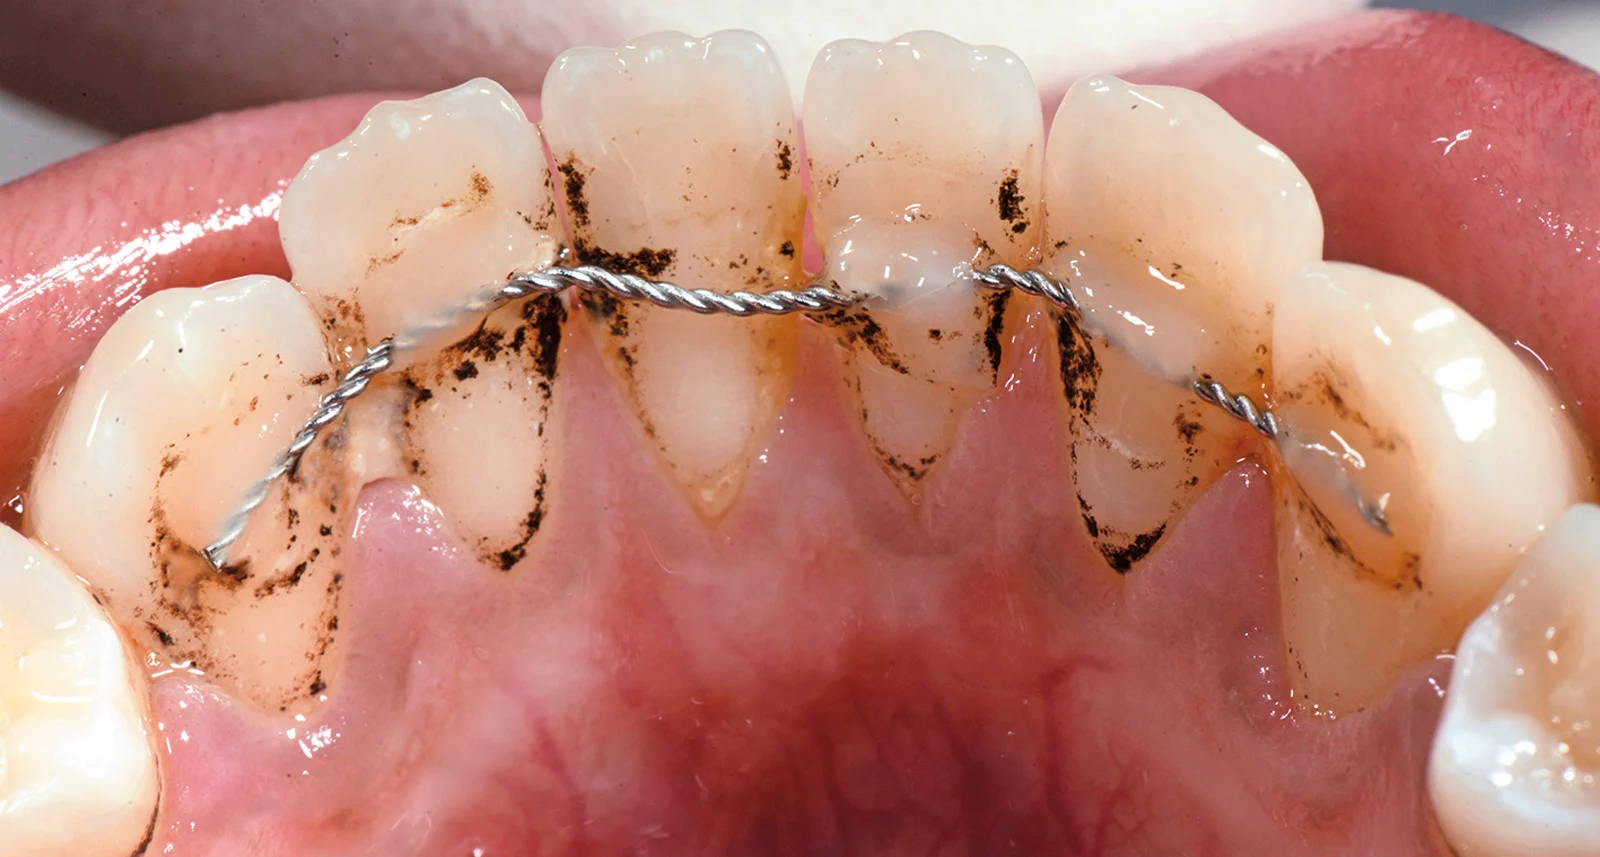

Svantaggi dei Retainers Fissi

- Igiene orale più complessa: Poiché il filo è attaccato ai denti, è più difficile pulire correttamente gli spazi interdentali. Il filo interdentale può essere utilizzato con uno scovolino o uno spazzolino interdentale per garantire una buona pulizia.

- Visite regolari: È necessario visitare regolarmente l’ortodontista per verificare lo stato del retainer e per controllare che non si stacchi o si danneggi.

Come Pulire un Retainer Fisso?

I retainers fissi richiedono un po’ più di attenzione durante la pulizia, poiché non possono essere rimossi dal paziente. È necessario un buon regime di igiene orale per garantire che il filo metallico e l’area circostante rimangano puliti.

- Spazzolare accuratamente: Spazzola i denti e il retainer fissi due volte al giorno, utilizzando uno spazzolino a setole morbide. Concentrati sul filo metallico e sui denti circostanti.

- Filo interdentale e scovolino: Poiché non è possibile usare il filo interdentale tradizionale, utilizza uno scovolino o filo interdentale speciale per pulire tra il filo del retainer e i denti. Questo aiuta a prevenire l’accumulo di placca.

- Visite regolari dall’ortodontista: Durante le visite di controllo, il dentista o l’ortodontista esaminerà la pulizia del retainer fisso e verificherà che non ci siano danni al filo o alla resina.

Suggerimenti:

- Presta particolare attenzione alla pulizia degli spazi tra il filo e i denti, dove i residui di cibo possono accumularsi facilmente.

- Assicurati di usare sempre uno spazzolino interdentale per evitare l’accumulo di placca e tartaro nei punti difficili da raggiungere.